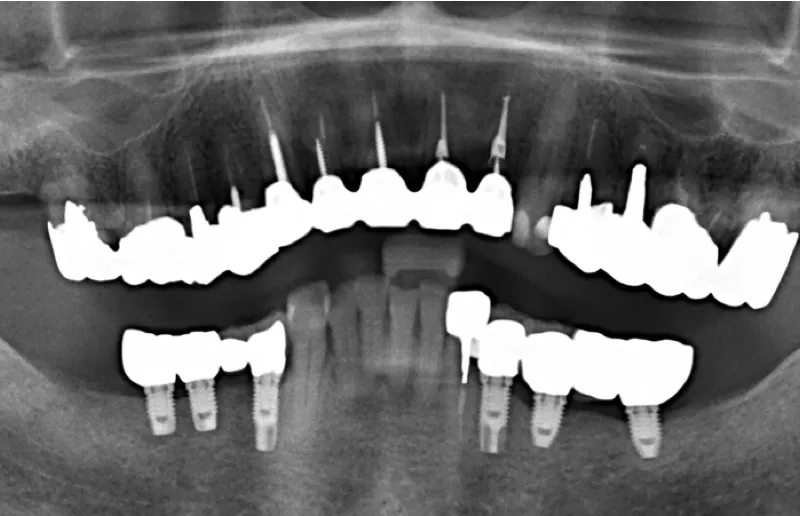

インプラントの本数については、奥歯で噛んだときの力を分散させるため、左右に3本ずつ埋めることをおすすめしました。

噛む力がとても強い患者様だったので、インプラント1本にかかる負担を少なくするほうがインプラントが長持ちすることをお伝えし、同意いただきました。

3ヶ月後、インプラントが骨としっかり定着したことを確認してから、左右同時に被せ物を作製し、インプラントの上に取り付けて治療を終了しました。

奥歯で違和感なく噛めるようになりました。